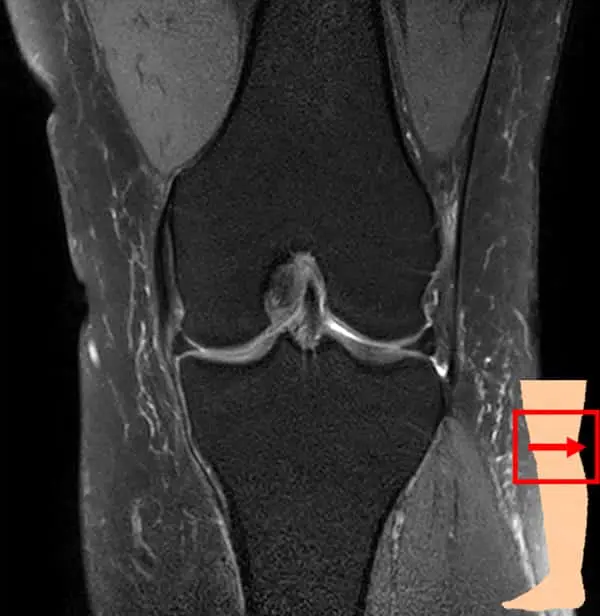

膝関節は大腿骨(太ももの骨)と脛骨(すねの骨)、腓骨(脛骨の外側にあるすねの骨)、膝蓋骨(膝のお皿)から構成されています。これらの骨を靱帯や筋肉、腱で繋いでおり、それらによって安定性を保っています。

膝関節の検査では、レントゲンの検査が一般的ですが、当クリニックではMRIを使用した検査を行なっています。

レントゲンよりも骨の内部や軟骨、半月板・靱帯の状態を把握できます。また、炎症や水が溜まっているかなどの確認も可能です。レントゲンとは違い、放射線被ばくもなく検査ができますので、体への負担が気になる方にもおすすめです。